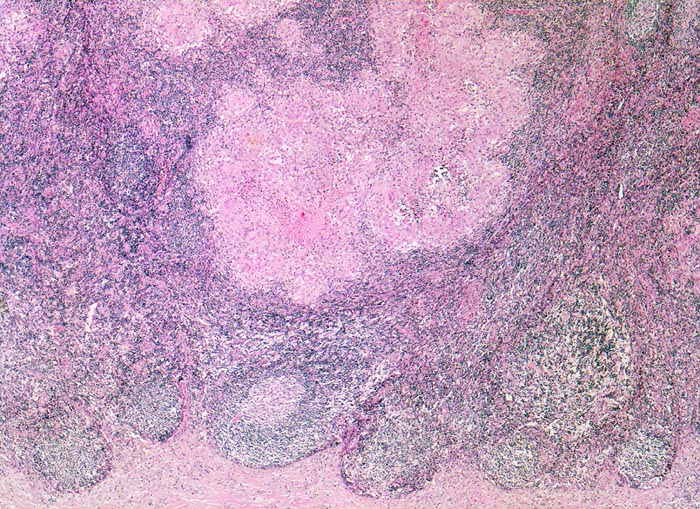

retikulozytär-abszedierende Lymphadenitis bei Katzenkratzkrankheit

Lymphknoten, Axilla

Unten im Bild die fibrosierte Lymphknotenkapsel. In der angrenzenden Rinde mehrere Lymphfollikel, eines davon mit Keimzentrum. Oben im Bild konfluierende histiozytäre Granulome mit zentraler Nekrose.

Nachweis von kleinen pleomorphen Bakterien

Keine käsige Nekrose wie bei Tbc.